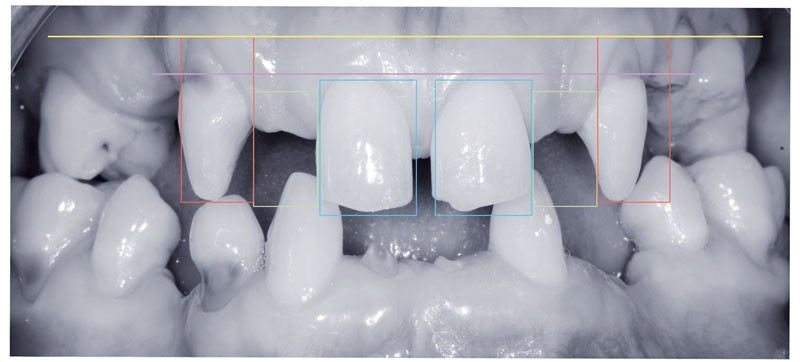

– trois photos antérieures intra-buccales : une en OIM (Occlusion d’Intercuspidation Maximale), une en bout à bout et une de la zone concernée du maxillaire ou de la mandibule avec un élément noir favorisant le contraste (« contrastor »).

Les figures 1 à 7 indiquent les impératifs à respecter, d’abord pour les portraits, puis pour les photos intra-buccales.